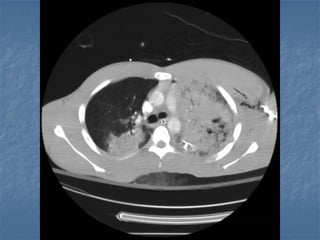

Surfactant Depletion followed by 4 hrs of Mechanical

ventilation

P/F-ratio:                 P/F -Ratio: 310

650

© B. Lachmann

Open Lung Strategy         ARDS Network Protocol